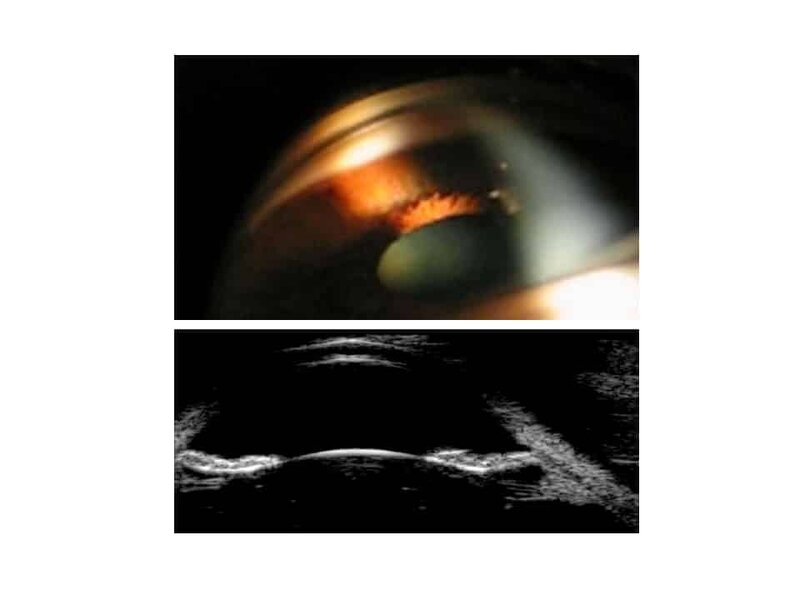

Fig 5 imagerie SA

Figure 5. Coupe du segment antérieur en biomicroscopie ultrasonore (UBM Aviso 25 MHz, haut): apposition de l’iris et de la face antérieure du cristallin et dépôts de pigments sur les fibres zonulaires. Coupes identiques en tomographie par cohérence optique (OCT Visante), avant (milieu) et après (bas) iridotomie.

Fig 6 imagerie SA

Figure 6. Concavité de l’iris en gonioscopie et coupe du segment antérieur en biomicroscopie ultrasonore (UBM Aviso 25 MHz, haut) montrant l’apposition de l’iris et de la face antérieure du cristallin et des dépôts de pigments sur les fibres zonulaires.